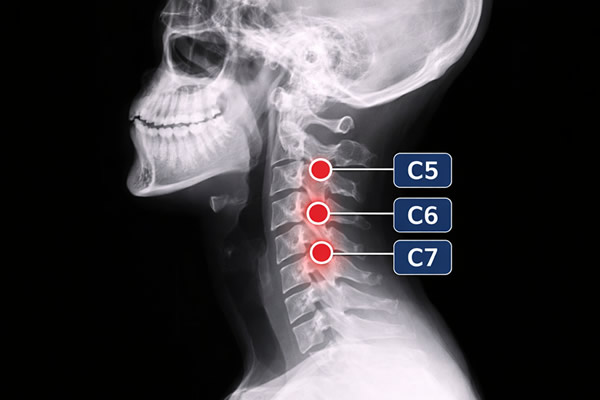

Las lesiones cervicales pueden ocurrir con cualquier seguimiento, pero son más frecuentes en la zona baja una vez que estos discos son responsables por soportar mayor carga y consecuentemente mayor estrés, que alteran sus capacidades funcionales.

C4-C5, C5-C6 y C6-C7 son las vértebras cervicales bajas (la parte media-inferior del cuello). Cuando una hernia se describe en alguno de estos seguimientos descritos anteriormente significa que el problema está en el disco situado entre esas vértebras, justo en esta zona del cuello que soporta mucha carga y movimiento. Por eso es uno de los puntos donde con más frecuencia aparece una hernia discal cervical.

En ese nivel, el disco puede protruir o herniarse hacia atrás y irritar/comprimir una raíz nerviosa cercana (y en casos habituales, estrechar el canal donde va la médula). Lo importante es entender que “C4-C5, C5–C6 y C6–C7” no son los únicos espacios que pueden ser afectados. Es un nombre técnico para indicar dónde está el origen del problema y por qué, desde ahí, pueden aparecer molestias que no se quedan solo en el cuello.